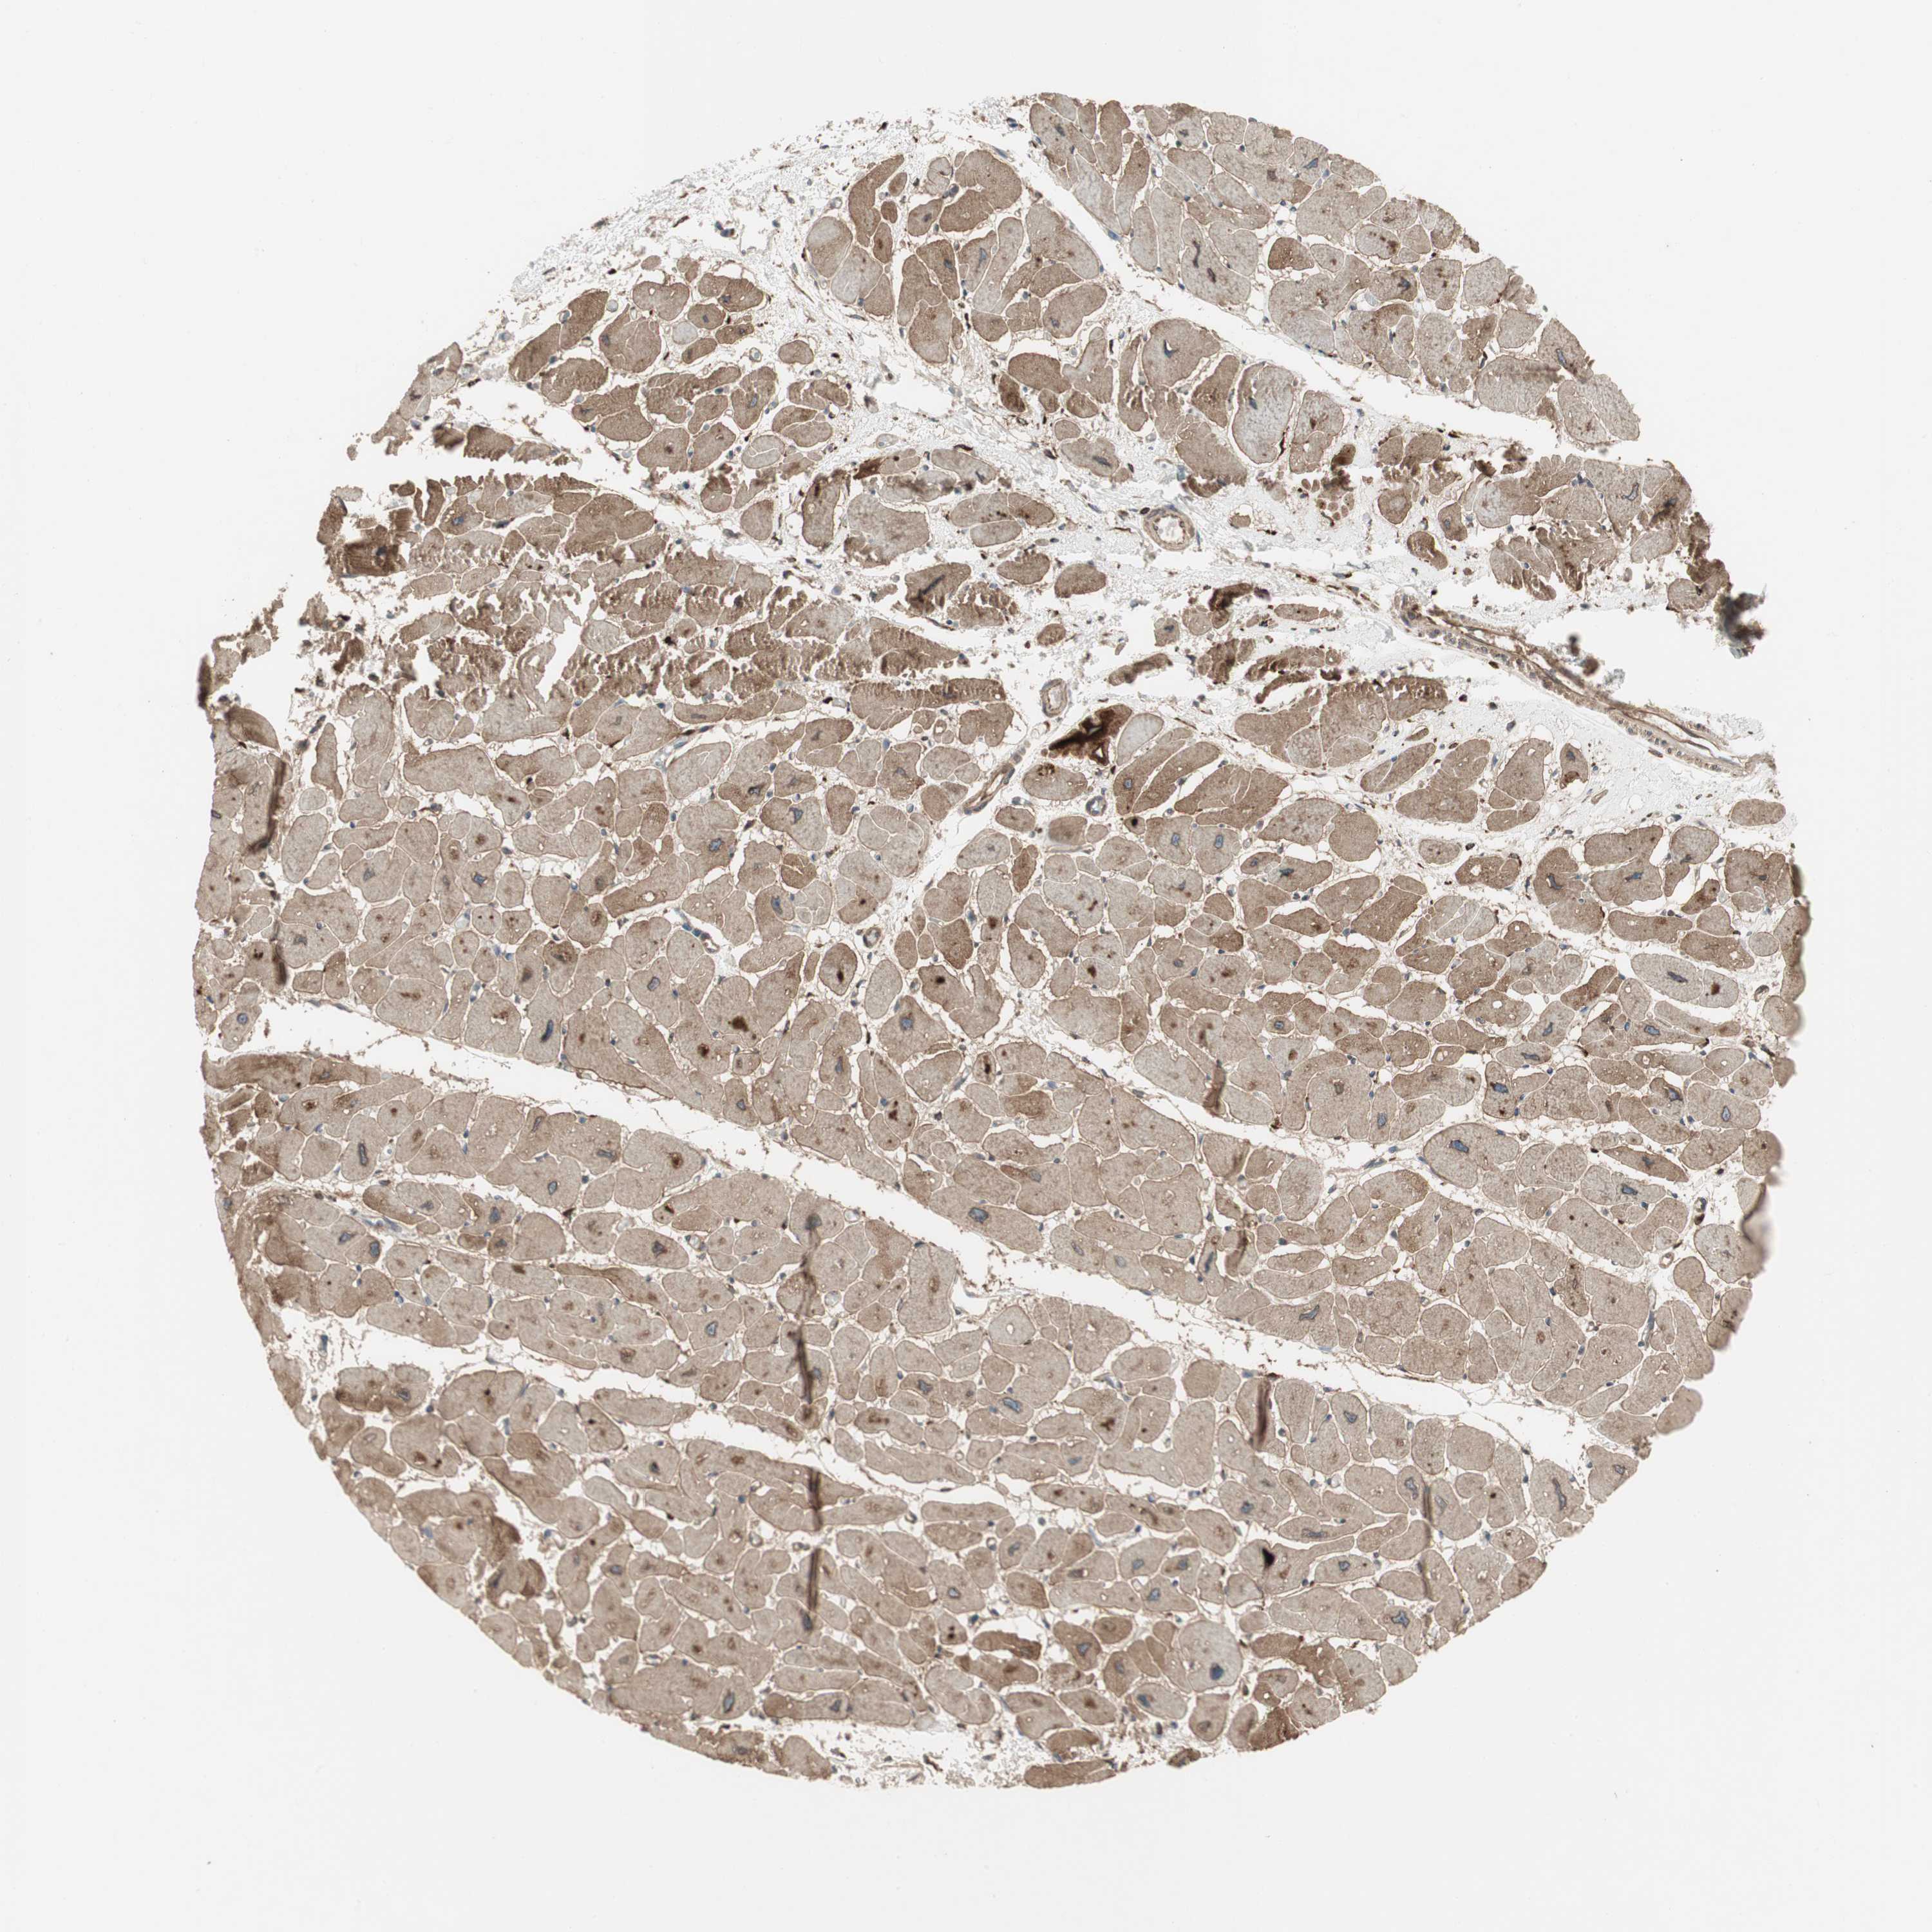

TISSUE PRIMARY DATA HEART MUSCLE Show tissue menu

HEART MUSCLE - Antibody stainingi

Antibody staining in the annotated cell types in the current human tissue is reported as not detected, low, medium, or high, based on conventional immunohistochemistry profiling in selected tissues. This score is based on the combination of the staining intensity and fraction of stained cells.

Each image is clickable and will lead to virtual microscopy that enables deeper exploration of all samples and also displays staining intensity scores, fraction scores and subcellular localization as well as patient and tissue information for each sample.

Antibody HPA007699Antibody CAB009629

Cardiomyocytes MediumMedium